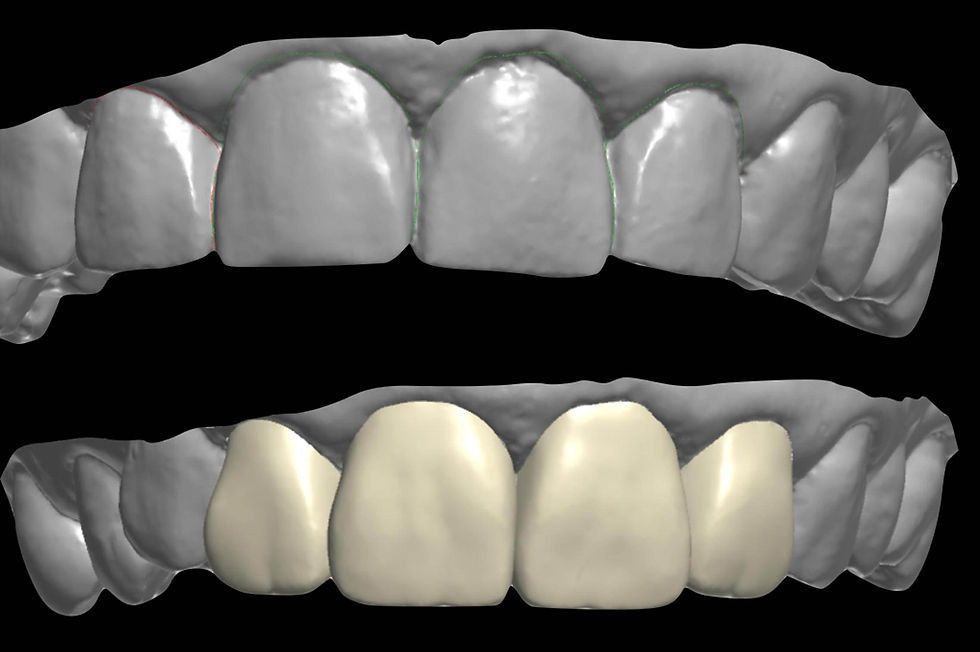

CAD-CAM planning of the definitive prosthesis.

Before the creation of the zirconia final structure, we verify the correct passivation through a biomedical resin model